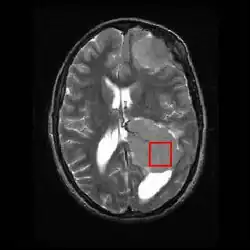

Spektroskopia rezonansu magnetycznego in vivo, w skrócie: in vivo MRS (od ang. in vivo magnetic resonance spectroscopy), in vivo MRI (od ang. in vivo magnetic resonance imaging), in vivo NMR (od ang. in vivo nuclear magnetic resonance) – wyspecjalizowana technika związana z obrazowaniem metodą rezonansu magnetycznego (RM)[1][2], stosowana głównie do badania guzów mózgu.

Umożliwia ona uzyskanie informacji o składzie biochemicznym w wybranych miejscach organizmu w sposób nieinwazyjny (bez konieczności wykonywania biopsji), podczas gdy RM dostarcza jedynie danych o budowie (strukturze) badanego narządu – na przykład gdy RM pokazuje, gdzie w ciele pacjenta jest zlokalizowany guz, spektroskopia rezonansu magnetycznego in vivo pozwala na określenie, jaki jest jego stopień złośliwości histologicznej.